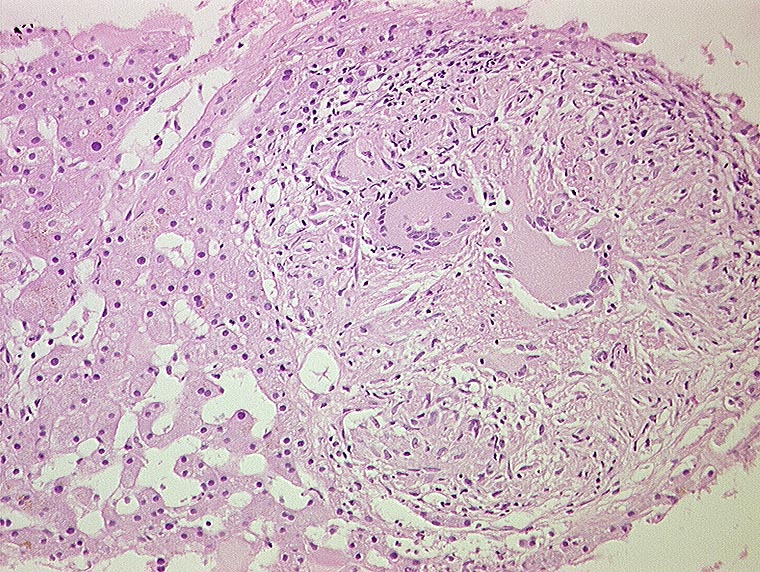

PathoPic ID 1247 - Miliartuberkulose : produktives Granulom

Miliartuberkulose : produktives Granulom

Entzündung infektiös

Leber

Nicht verkäsendes produktives Granulom aus Epitheloidzellen und Langhans'schen Riesenzellen mit hufeisenförmig angeordneten Kernen.

Histologie